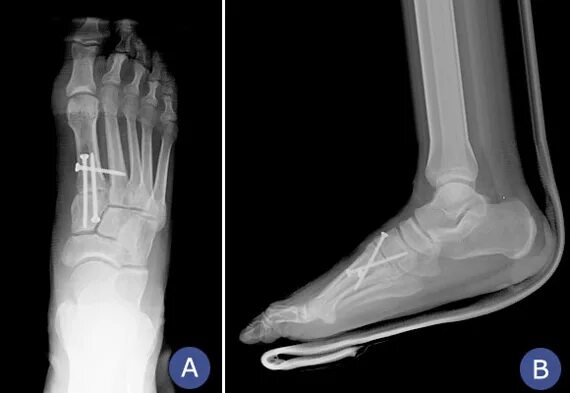

Пяточная остеотомия